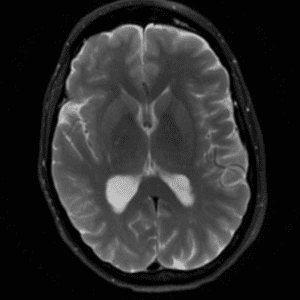

Brain Tumor Practice Cases

Case #5

Neurofibromatosis type II